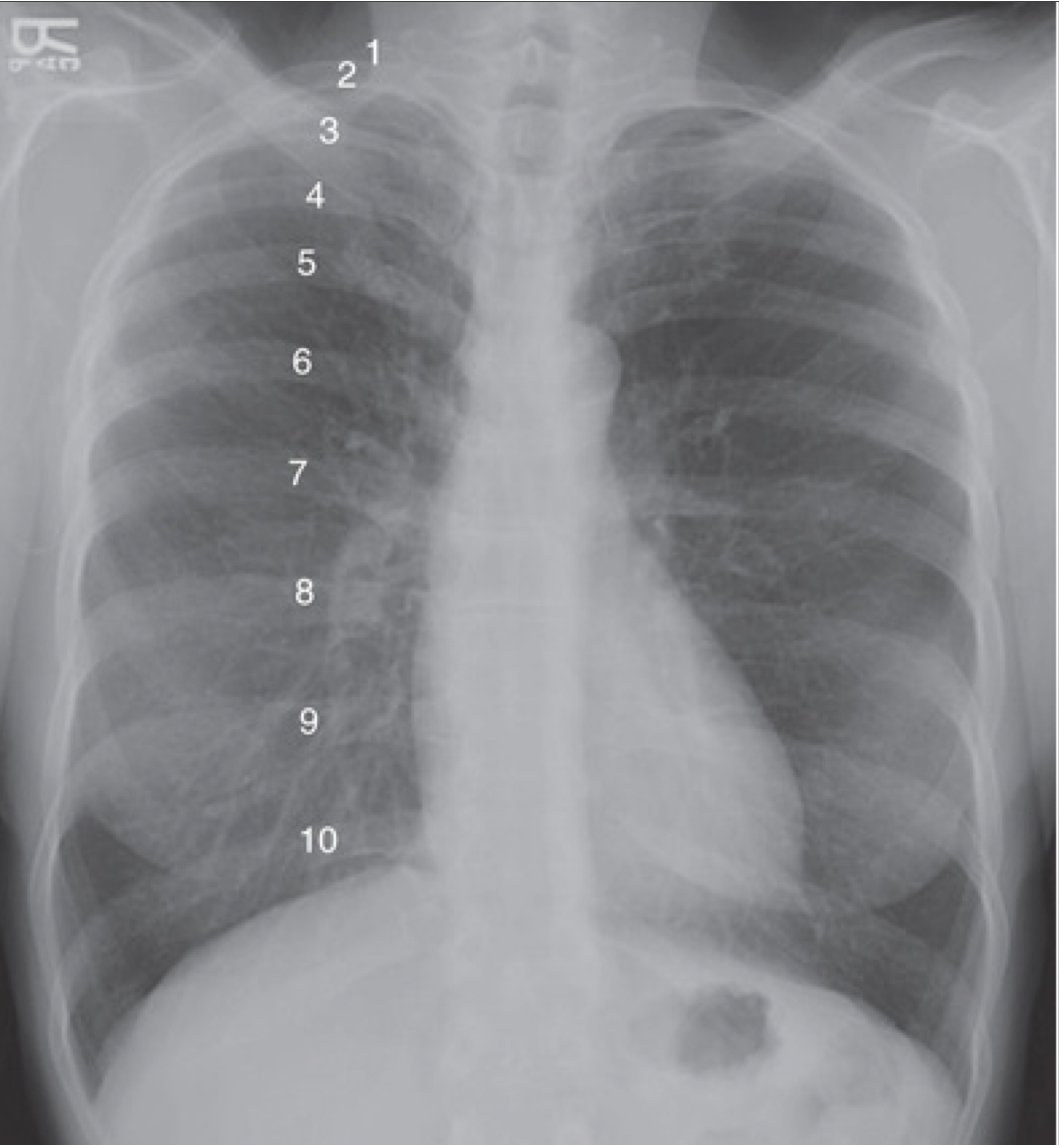

inspiration

fills lungs adn contracts diaphragm

10 posterior ribs are visible above diaphragm

8-9 in hospitalized pts

suboptimal inspiration

compress and crowd the lung markings at the llung bases adn diaphram

could be misleading of pneumonia or cardiomegaly

only 7 posterior ribs visible